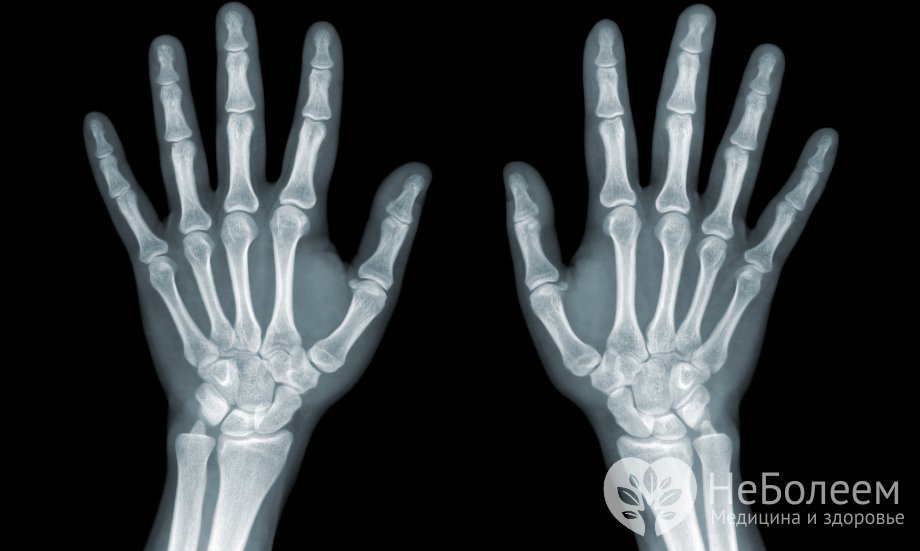

Кости запястья образует совокупность из 8 маленьких губчатых костей, которые располагаются в два ряда, в каждом из которых находится по 4 косточки.

Первый или проксимальный ряд, расположенный ближе к предплечью, состоит из следующих костей, представленных по порядку, начиная с большого пальца:

ладьевидной или os scaphoideum;

полулунной или os lunatum;

трехгранной или os triquetrum;

гороховидной или os pisiforme.

Соединение первых трех косточек образует эллиптическую суставную поверхность, которая сочленяет запястье и дистальный конец лучевой кости. Гороховидная кость запястья, которую принято относить к сесамовидной косточке, в свою очередь, присоединена к трехгранной кости.

Второй ряд костей запястья – дистальный – образован следующими косточками:

трапецией или os trapezium;

трапециевидной или os trapezoideum;

головчатой или os capitation;

крючковидной или os hamatum.

Поверхность каждой кости снабжена специальными суставными фасетками, которые помогают косточкам соединяться с ближайшими костями. Также на ладонных поверхностях ряда костей запястья располагаются бугорки, к которым крепятся связки и мышцы. К таким костям относятся: ладьевидная, трапеция, крючковидная.

Общий вид костей запястья имеет форму свода, выпуклая часть которого расположена на тыльной стороне ладони, вогнутая – на ладонной.

Практически все 8 костей запястья имеют шесть поверхностей (кроме гороховидной). При этом все кости без исключения относятся к суставным: нижняя их поверхность формирует суставные ямки, а верхняя – суставные головки. Между боковыми поверхностями костей также есть сочленения, связывающие кости запястья между собой.